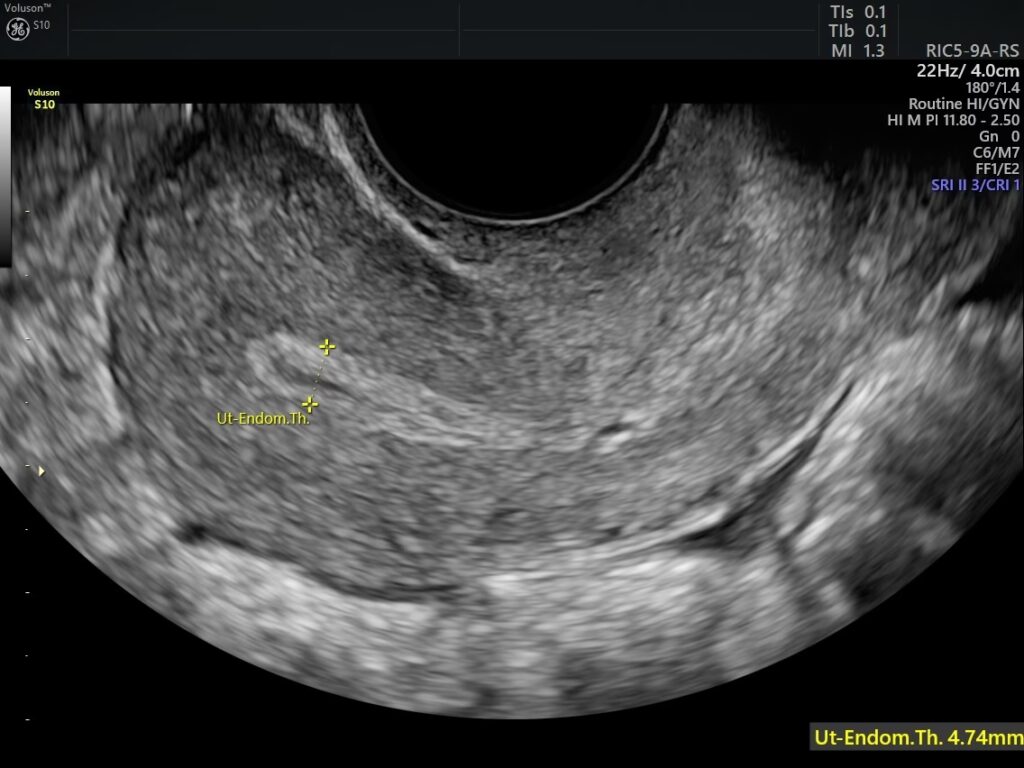

Den mest almindelige og præcise metode til at måle endometriets tykkelse er en transvaginal ultralydsscanning. Ved denne undersøgelse føres en lille ultralydsprobe ind i skeden, hvilket giver et meget detaljeret og klart billede af livmoderen og dens slimhinde. Lægen eller sonografen måler tykkelsen i sagittalplanet (et snit på langs af livmoderen) på det tykkeste sted. Målingen omfatter hele tykkelsen fra den ene basale overflade til den anden, uden at medtage eventuel væske i livmoderhulen.

I nogle tilfælde kan en MR-scanning også anvendes til at vurdere endometriet, men ultralyd er den foretrukne metode på grund af dens tilgængelighed og nøjagtighed til netop denne måling.